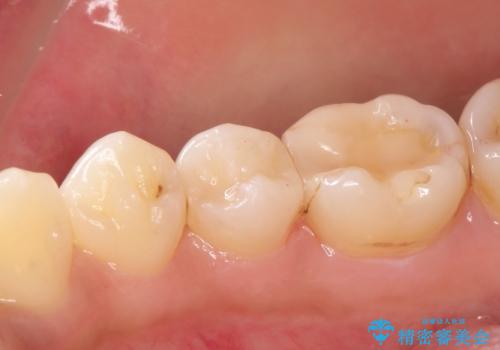

顕微鏡下で丁寧に虫歯を取り除き、セラミックインレーによる修復治療を行いました。

- セラミックインレー7万円費用は治療当時の料金となります

虫歯が大きく広がっていましたが、顕微鏡を使って慎重に治療を行うことで、神経をとってしまうことなく治療することができます。